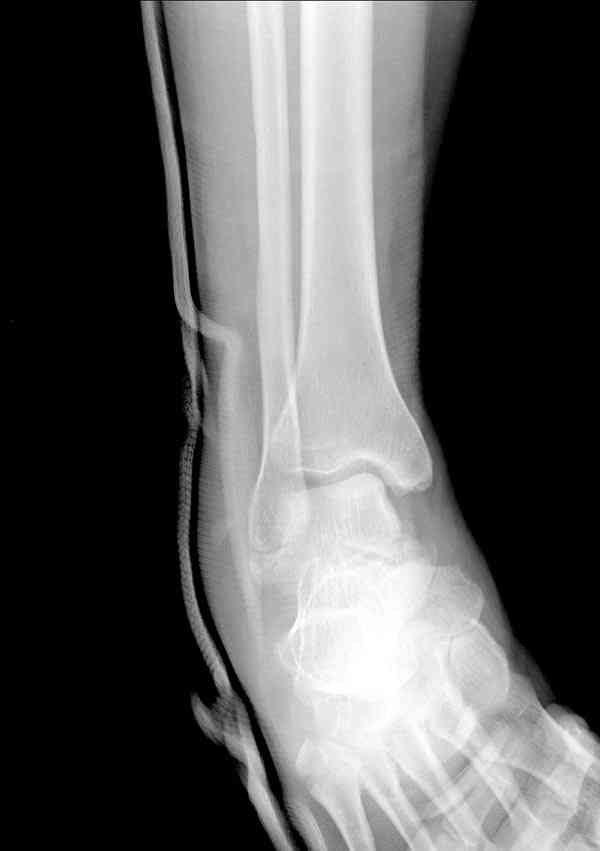

а основании двух видов ренгенограмм невозможно радикально решить о необходимости открытой репозиции или первичного артродеза.

Для оценки состояния нужны дополнительные исследования, например Canale или Broden ренгенограммы и Компьютерная томография.

При переломах тарана всегда имеется риск AVN, а классификация Hawkins поможет разобраться с предполагаемыми осложнениями.

Если в первом типе, когда перелом шейки без смещения, тогда AVN менее 10%, при втором типе когда имеется смещение и вывих тарана в субталарном сочленении меньше 40%, а при типе III когда смещение в голеностопном и субталарном суставах - около 90% и в типе IV, когда происходит полный вывих, риск AVN достигает 100%.

Многие переломы тарана сопровождается открытой раной, в 20% встречаются раны передненаружные, а в 50% переломы типа Hawkins III являются открытыми, и в 40% раны осложняются инфекцией.

Идеально фиксацию провести в первые часы, но не всегда возможно из-за отека, поэтому временный наружный фиксатор на дистракцию поможет уменьшению отека и даст время для адекватного обследования.

При в первом типе придерживаемся закрытой репозиции, а у всех остальных в зависимости от смещения предпочитаем открытую репозицию, фиксация шурупами или пластиной. Пластина 2.4 мм более предпочтительна для удержания мелких костных осколков.

В вашем случае доступ через перелом медиальной лодыжки, обычный доступ через остеотомии лодыжки, где имеется возможность прямой репозиции тарана, после фиксации шурупами, лодыжки фиксируются обычным 2х лодыжечным методом.

Предпочтительно выжидательная тактика, чем радикальный первичный артродез.

Множество наблюдений больных с аваскулярным некрозом, где место тарана заполнялось фиброзной матрицей и жалоб особых не проявляли.

Случай с множественным оскольчатым переломом тарана оперированный из двойного доступа.